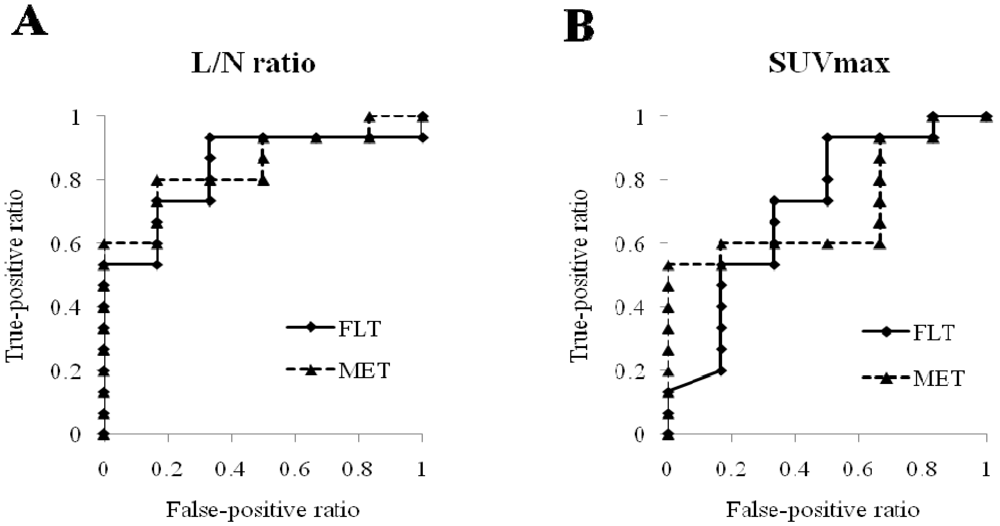

2.1.2. Semi-Quantitative Analysis

2.2. Discussion